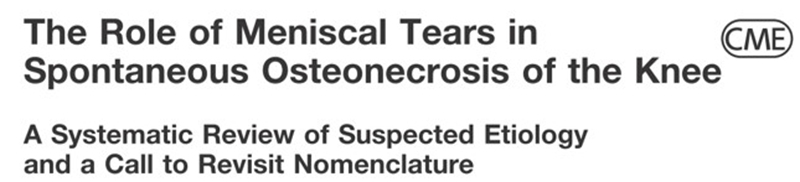

SONK的真正病因尚不清楚,目前主要3种学说:①创伤源性理论,股骨髁在机械应力作用下发生软骨下区微骨折;②血管源性理论,股骨髁血供中断导致局部血液循环障碍;③应力源性理论,半月板损伤、突出和膝内翻。

③应力源性理论:

关于SONK与内侧半月板损伤,在一项研究中,关节造影检查27个SONK膝关节中发现有21个(78%)半月板撕裂,半月板碎片边缘的应力集中可能导致股骨髁缺血性坏死。

表明老年患者通过关节造影早期发现内侧半月板撕裂并及时治疗,对于避免“自发性”骨坏死的晚期变化可能很重要。

另一项研究纳入26篇文章,其中有21篇(80.7%)涉及半月板在SONK发展中的作用,启示SONK与半月板撕裂或半月板切除术后的发展有关,而内侧半月板撕裂、后根撕裂更常见。

SONK与内侧半月板后根部损伤,有国外学者在SONK患者中通过MRI及关节镜检查,常可发现合并内侧半月板后根部的撕裂,该发生率可达到80%(24/30), 15例完全撕裂,9例部分撕裂。结果表明SONK可能与内侧半月板后根部撕裂后,导致股骨负重区的应力集中、软骨下骨髓水肿有关。